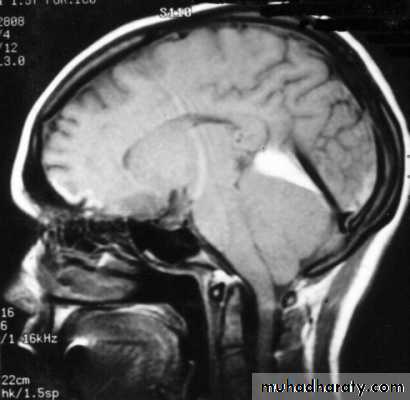

2. Obstruction to CSF pathways: as seen in:

a. Obstructive hydrocephalus.

b. Communicating hydrocephalus.